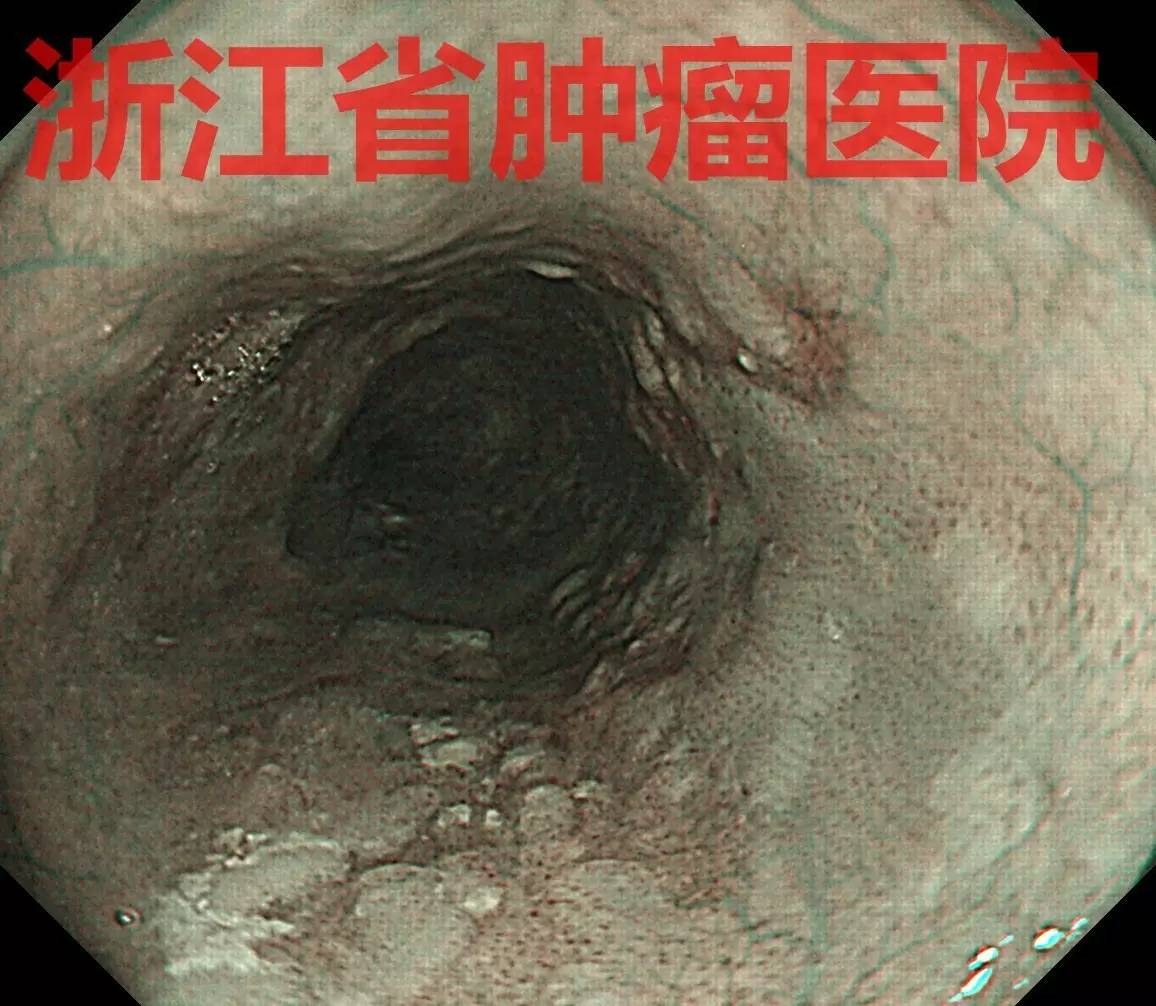

食管中段距门齿25-30 cm约3/4周黏膜粗糙充血,边界不清,表面见有异常白色角化物质附着,局部有黏膜缺损表现。

NBI弱放大可见病变管壁近全周见棕褐色,几乎没有正常背景。表面有多发白色物质附着。